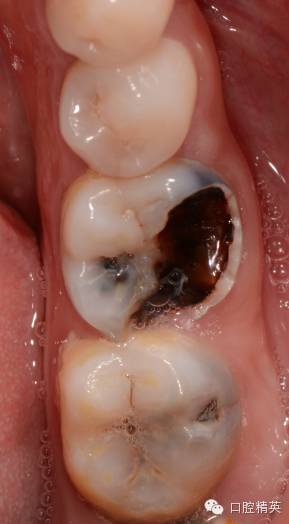

开髓,揭净髓顶,直线通道车针逐步建立直线通路,大量次氯酸钠冲洗,探查根管长度,次氯酸钠和edta交替冲洗根管

tf镍钛锉预备至30#06锥度(虽然根尖区域的预备应该在35#~40#)但我认为这不是根尖周炎,所以仅仅预备到30#,大量次氯酸钠荡洗根管,根充还是用的iroot糊剂和热牙胶,我用的是思博安的热牙胶,很多同行和我说,相比韩国的产品思博安的成本太高了,但思博安的牙胶是 β象限的,低温时的流动性更好,更容易进入狭窄部位和侧支根管,所以我认为,相对与更好的治疗效果,成本并不重要。

近中根管的侧枝清晰可见